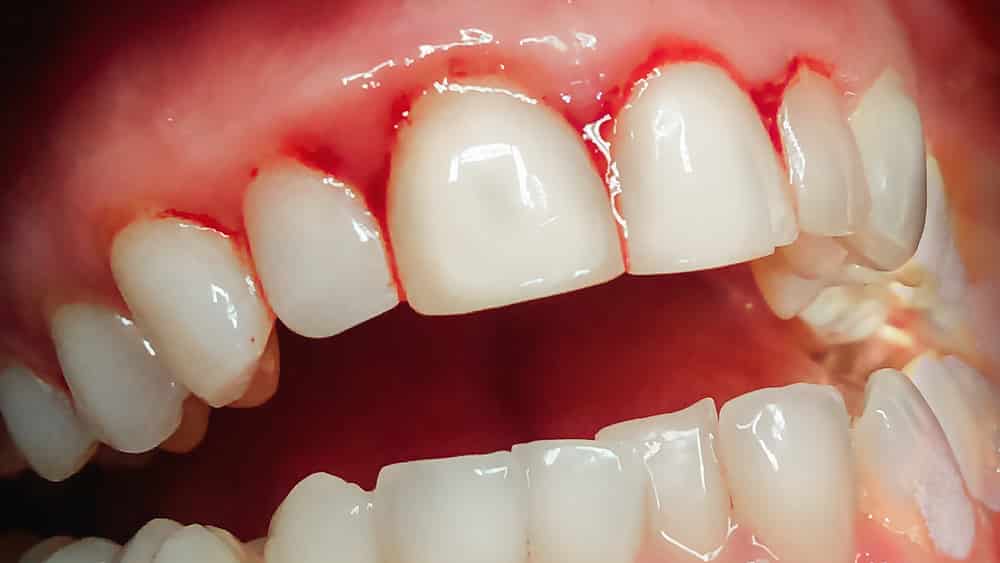

Vamos falar sério sobre gengiva. Você sabia que sangrar ao escovar os dentes ou usar fio dental não é normal? Pois é, muita gente ignora, mas esse é um dos primeiros sinais de que algo não vai bem. A gengivite, que começa com um simples incômodo, pode evoluir e virar um problemão se não cuidarmos. Se a sua gengiva anda machucando, fique atenta!

Quando a gengivite se agrava, ela pode causar o que chamamos de “gengivite expulsiva”. Isso significa que a gengiva começa a se afastar dos dentes, criando espaços onde sujeira e bactérias se acumulam ainda mais. Imagina só, os dentes parecem mais longos e até a sensibilidade pode aumentar. É um sinal claro de que a saúde bucal precisa de atenção urgente.

Dica Prática: Se sentir dor ou sangramento ao escovar, mesmo com cuidado, procure seu dentista. Não ignore esses sinais.

Sim, se não for tratada, a gengivite pode afetar o osso que segura seus dentes. Isso pode levar à perda dentária. Cuide logo para evitar maiores problemas.